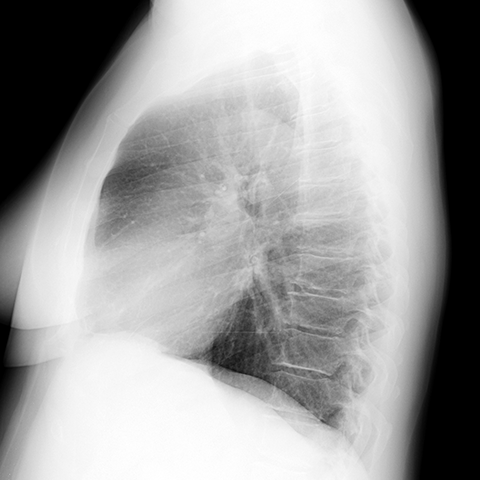

Normal anatomy of the lungs (CXR) [8 of 8]

Lines

Lines and Labels